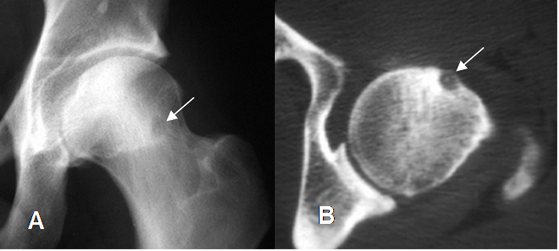

Fig 59. Osteoma osteoide.

A: Rx AP y B: TAC axial. Imagen en el cuello femoral, con nido denso, por osteoma osteoide.